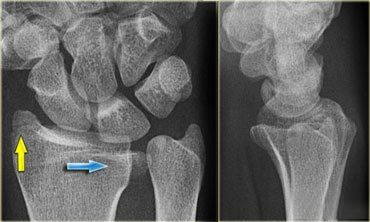

(6)Hutchinson 骨折

又名Chauffeur 骨折、back-fire 骨折、crank 骨折。是桡骨茎突斜行骨折,累及桡腕关节。